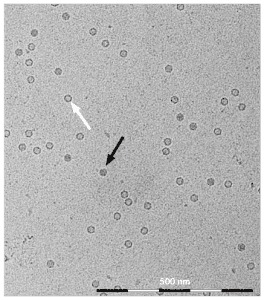

Figure 2: Cryo TEM picture from AAV particles derived from ELEVECTA® Producer Cell Lines. The viral particles display an approximate size of 22 nm. Full particles are indicated by a black arrow, empty particles by a white arrow

AAV vectors can have different surface structures, so called serotypes, which in nature allow the virus to target specific cells in a body. For gene therapy applications viral serotypes can further be engineered to improve their tissue-specificity and safety. Every ELEVECTA producer cell line is custom-made and employs a specific natural or engineered capsid gene and the therapeutic gene of interest.